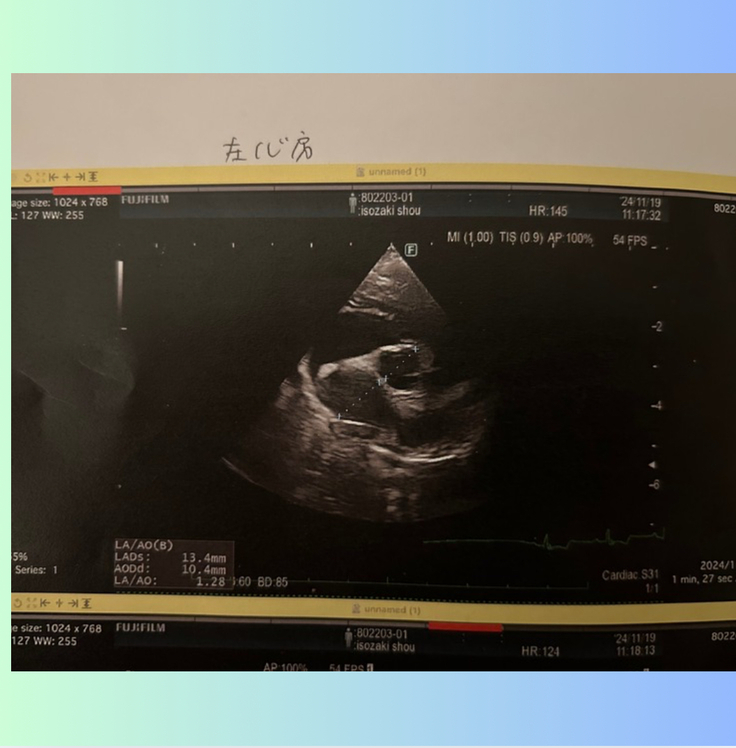

左心房の大きさは....

手術前は、2.5倍に肥大していましたが、

2ヶ月検診では、1.28まで小さくなっていました。